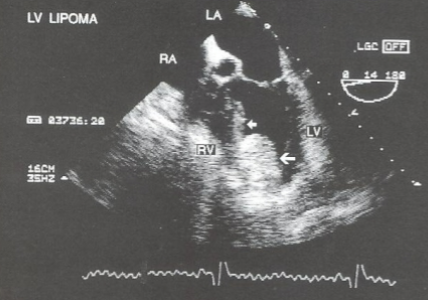

Lipoma

neoplasm of mature fat cells

well-defined, homogenous, dense mass

can invade all 3 heart layers

Where are Lipomas usually located?

LV

RA

IAS